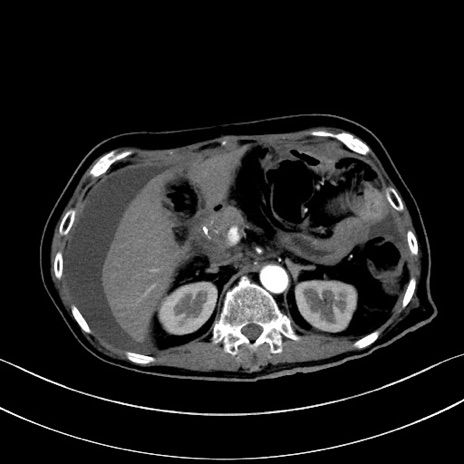

症例28(横断像)

【症例】60歳代男性

【主訴】嘔吐

【現病歴】胃癌にて胃全摘後。食思不振が悪化し、夜中に嘔吐することがある。

【既往歴】胃癌、胃全摘、脾摘、胆摘後

【データ】WBC 5900、CRP 10.56